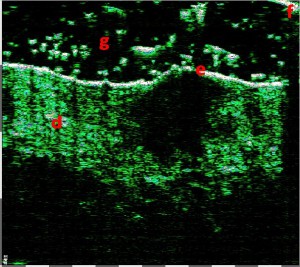

Σάρωση μελανώματος 75 MHz, υποανηχοϊκός όγκος

11 mm x 300 μm,

βάθος 140-190 μm από την επιφάνεια του δέρματος

ΔΕΙΚΤΗΣ BRESLOW – 0

(πάχος μελανώματος 0,28-0,3 mm)

ΕΠΙΠΕΔΟ CLARK – 2 (διείσδυση στο θηλώδες χόριο)

Η έγκαιρη ΜΗ ΕΠΕΜΒΑΤΙΚΗ αξιολόγηση της εξάπλωσης του όγκου (πάχος και επίπεδο διείσδυσης) πριν από τη θεραπεία έχει θεμελιώδη σημασία, καθώς επιτρέπει όχι μόνο τη διάγνωση, αλλά και την αποφυγή υπερδιάγνωσης. Η αξιολόγηση του μεγέθους και του σταδίου του όγκου με Υπέρηχο Υψηλής Συχνότητας – HFUS επιτρέπει την επιλογή της κατάλληλης χειρουργικής επέμβασης για την αφαίρεσή του, τον σχεδιασμό των πρόσθετων διαγνωστικών διαδικασιών για την αναζήτηση απομακρυσμένης μετάστασης, καθώς και τον σχεδιασμό της επικουρικής χημειοθεραπείας και ανοσοθεραπείας. Είναι σημαντικό, σε περίπτωση μελανώματος, ο υπερηχογράφος δέρματος υψηλής συχνότητας να επιτρέπει στον χειρουργό να σχεδιάζει τον όγκο της εκτομής ακριβώς σύμφωνα με τον δείκτη Breslow in vivo πριν από την επέμβαση.